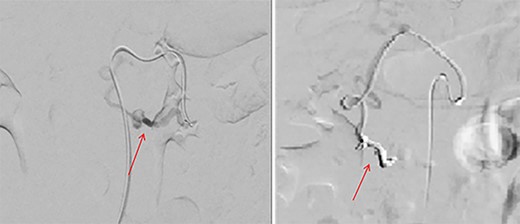

Initially, the main diagnosis considered was an aortic dissection. Other initial general surgical differentials were a perforated viscous or severe pancreatitis. Computed tomography (CT) angiogram showed a 6 mm pseudoaneurysm arising from a branch vessel 3 cm distal to the origin of the SMA. There was no active arterial blush; however, there was a large associated mesenteric haematoma (measuring 4.5 × 8.0 × 13 cm) with large volume haemoperitoneum (Figs 1–3). There was also a splenic artery aneurysm measuring 5 mm with no evidence of active haemorrhage. After the CT scan, she was noted to be haemodynamically unstable when lying supine, due to inferior vena cava compression by the mesenteric haematoma. A pillow was placed under her left lateral side to act as a wedge to reduce this. She proceeded to urgent angioembolization by interventional radiology, which confirmed the pseudoaneurysm on angiography (Fig. 4, left). The SMA was accessed and the aneurysm was successfully embolized with 3 mm diameter 15 cm length Ruby micro-soft detachable coil (Fig. 4, right).

Pre-embolization (left) and post-embolization with coils (right).